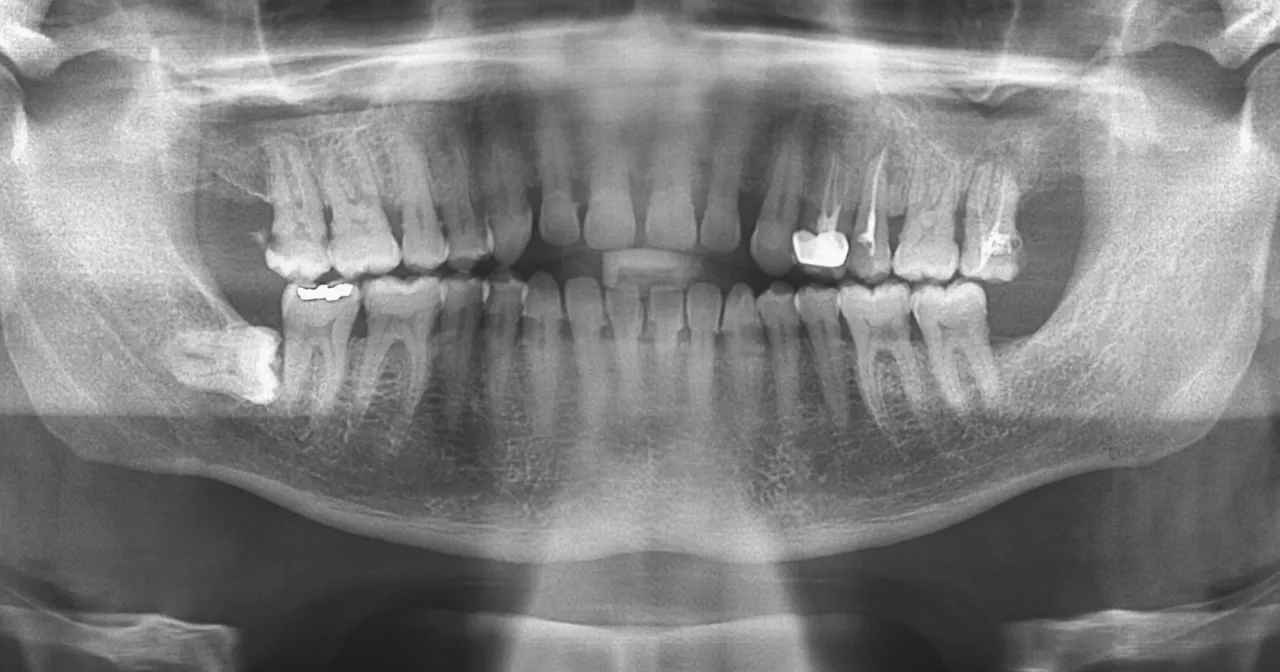

Kiedy patrzę na zdjęcie panoramiczne, widzę prawdziwą mapę jamy ustnej pacjenta. To kompleksowy obraz, na którym mogę dokładnie ocenić wiele kluczowych elementów:

- Wszystkie zęby: Zarówno te wyrżnięte, jak i te, które jeszcze czekają na swój moment, na przykład niewyrżnięte ósemki czy zęby nadliczbowe.

- Korzenie zębów: Ich kształt, długość, położenie, a także ewentualne zmiany zapalne wokół wierzchołków.

- Kości szczęki i żuchwy: Mogę ocenić ich gęstość, strukturę, a także obecność ewentualnych ubytków kostnych, na przykład w przebiegu chorób przyzębia.

- Stawy skroniowo-żuchwowe: Patrzę na ich budowę i ewentualne zmiany, które mogą być przyczyną dolegliwości bólowych czy problemów z otwieraniem ust.

- Zatoki szczękowe: Chociaż pantomogram nie jest badaniem dedykowanym do szczegółowej oceny zatok, pozwala mi na wstępne zauważenie zmian, takich jak stany zapalne czy obecność torbieli.

- Zmiany patologiczne: Mogę wykryć torbiele, guzy, a także ocenić jakość wcześniejszych wypełnień czy leczenia kanałowego.

Analiza pantomogramu to dla mnie jak czytanie otwartej księgi o zdrowiu jamy ustnej pacjenta. Na zdjęciu panoramicznym widzę nie tylko korony zębów, ale przede wszystkim ich korzenie ich długość, kształt, a także ewentualne zmiany zapalne wokół ich wierzchołków, które mogą świadczyć o martwicy miazgi lub przewlekłych infekcjach. Równie ważna jest ocena stanu kości szczęki i żuchwy. Zwracam uwagę na gęstość kości, obecność ubytków kostnych, na przykład w przebiegu zaawansowanej paradontozy, a także na wszelkie nieprawidłowości w ich strukturze. To pozwala mi ocenić ogólną kondycję podłoża dla zębów i zaplanować ewentualne zabiegi, takie jak wszczepienie implantów.

Ukryci wrogowie, których ujawnia pantomogram: próchnica, stany zapalne i torbiele

Pantomogram jest niezastąpiony w wykrywaniu "ukrytych wrogów", czyli patologii, które są niewidoczne podczas standardowego badania klinicznego. Często na zdjęciu panoramicznym ujawnia się próchnica, zwłaszcza ta międzyzębowa, która rozwija się w trudno dostępnych miejscach i jest trudna do zdiagnozowania bez RTG. Widzę również stany zapalne wokół wierzchołków korzeni, które mogą być bezobjawowe, a jednak stanowią poważne zagrożenie dla zdrowia zęba i całego organizmu. Ponadto, pantomogram pozwala na wczesne wykrycie torbieli i guzów w obrębie kości szczęki i żuchwy. Wczesne wykrycie tych zmian jest absolutnie kluczowe dla skutecznego leczenia i zapobiegania poważniejszym komplikacjom.Zęby zatrzymane i ósemki: kluczowe znaczenie pantomogramu przed usunięciem

W przypadku zębów zatrzymanych, a w szczególności ósemek, pantomogram jest dla mnie narzędziem diagnostycznym o kluczowym znaczeniu. Przed podjęciem decyzji o ekstrakcji, muszę dokładnie ocenić położenie zęba, jego orientację, głębokość, a także bliskość do ważnych struktur anatomicznych, takich jak nerw zębodołowy dolny czy zatoka szczękowa. Zdjęcie panoramiczne dostarcza mi tych wszystkich informacji, pozwalając na precyzyjne zaplanowanie zabiegu chirurgicznego. Dzięki temu mogę zminimalizować ryzyko powikłań, takich jak uszkodzenie nerwu czy otwarcie zatoki, co jest niezwykle ważne dla bezpieczeństwa pacjenta.

Chociaż pantomogram koncentruje się na uzębieniu, jego zakres obrazowania jest szerszy. Na zdjęciu panoramicznym mogę również wstępnie ocenić stawy skroniowo-żuchwowe (SSŻ). Widzę ich ogólną budowę, symetrię, a także ewentualne zmiany degeneracyjne czy nieprawidłowości w ich położeniu. Chociaż do szczegółowej diagnostyki SSŻ często potrzebne są bardziej zaawansowane badania, pantomogram daje mi cenne wskazówki. Podobnie jest z zatokami szczękowymi na zdjęciu widoczne są ich dolne części, co pozwala mi na wstępne zauważenie zmian zapalnych, pogrubienia błony śluzowej czy obecności torbieli retencyjnych. To często pierwszy sygnał, że pacjent może potrzebować konsultacji laryngologicznej.